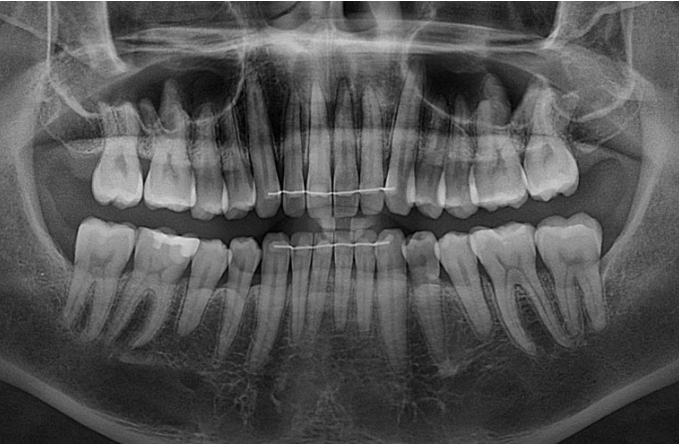

치근흡수 없이 치근평행도도 양호합니다.